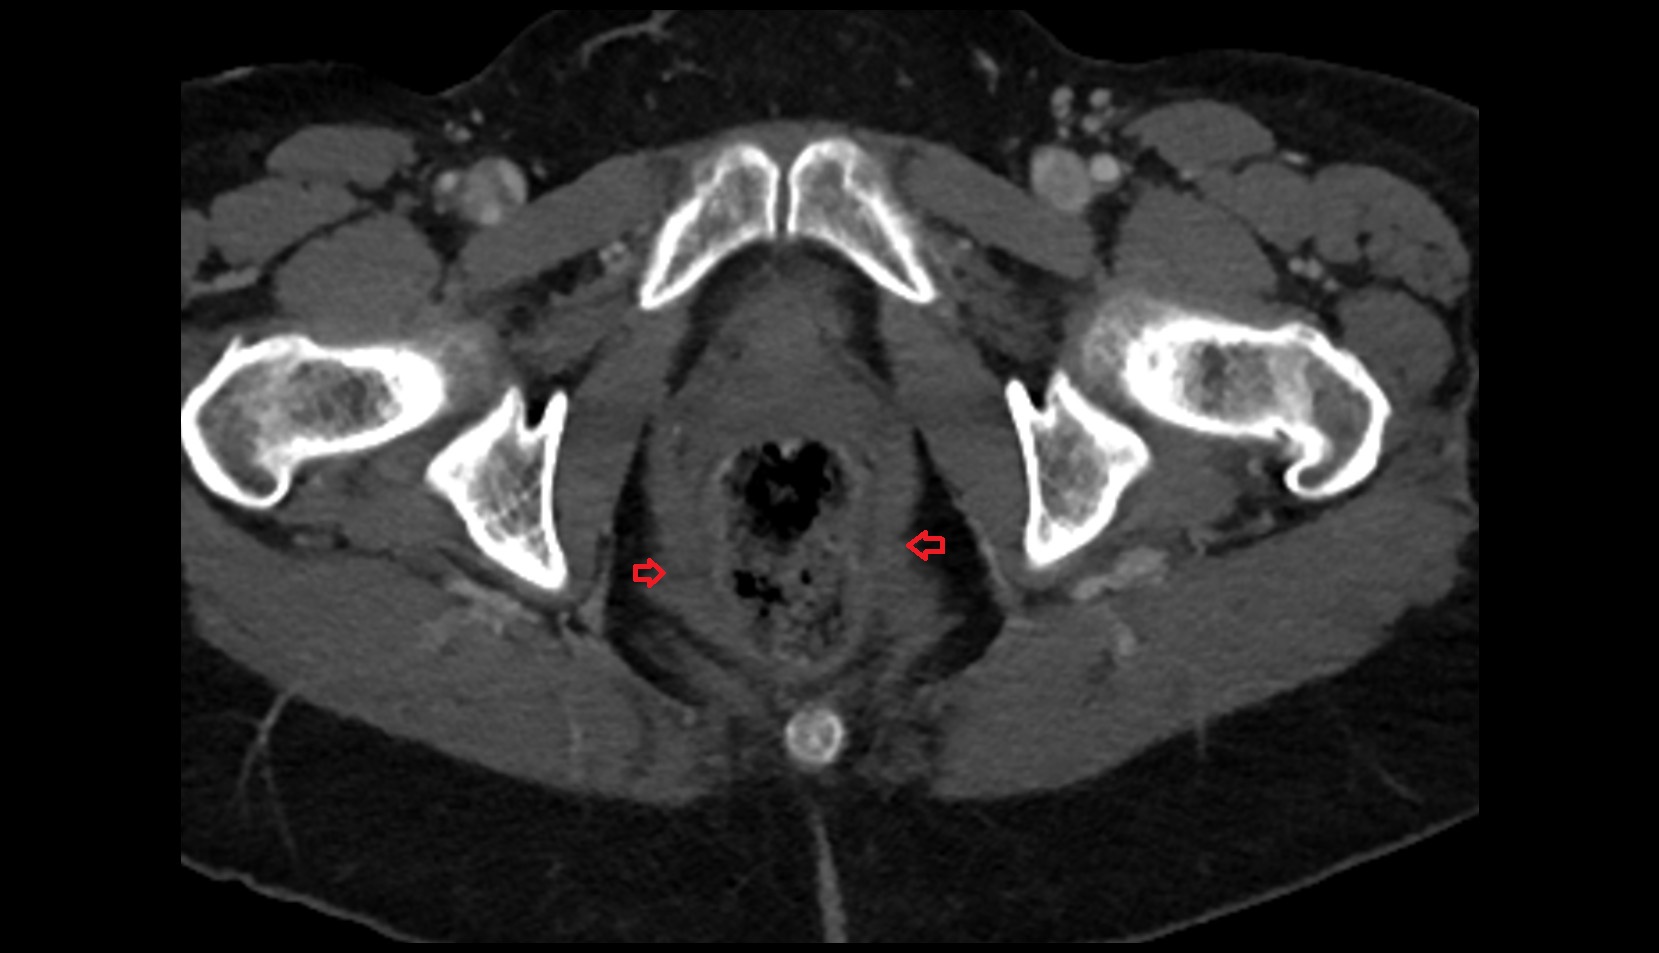

- Peripheral zone of prostate

- Anterior Fibromuscular Stroma of prostate

- Central zone of prostate

- Transitional zone of prostate